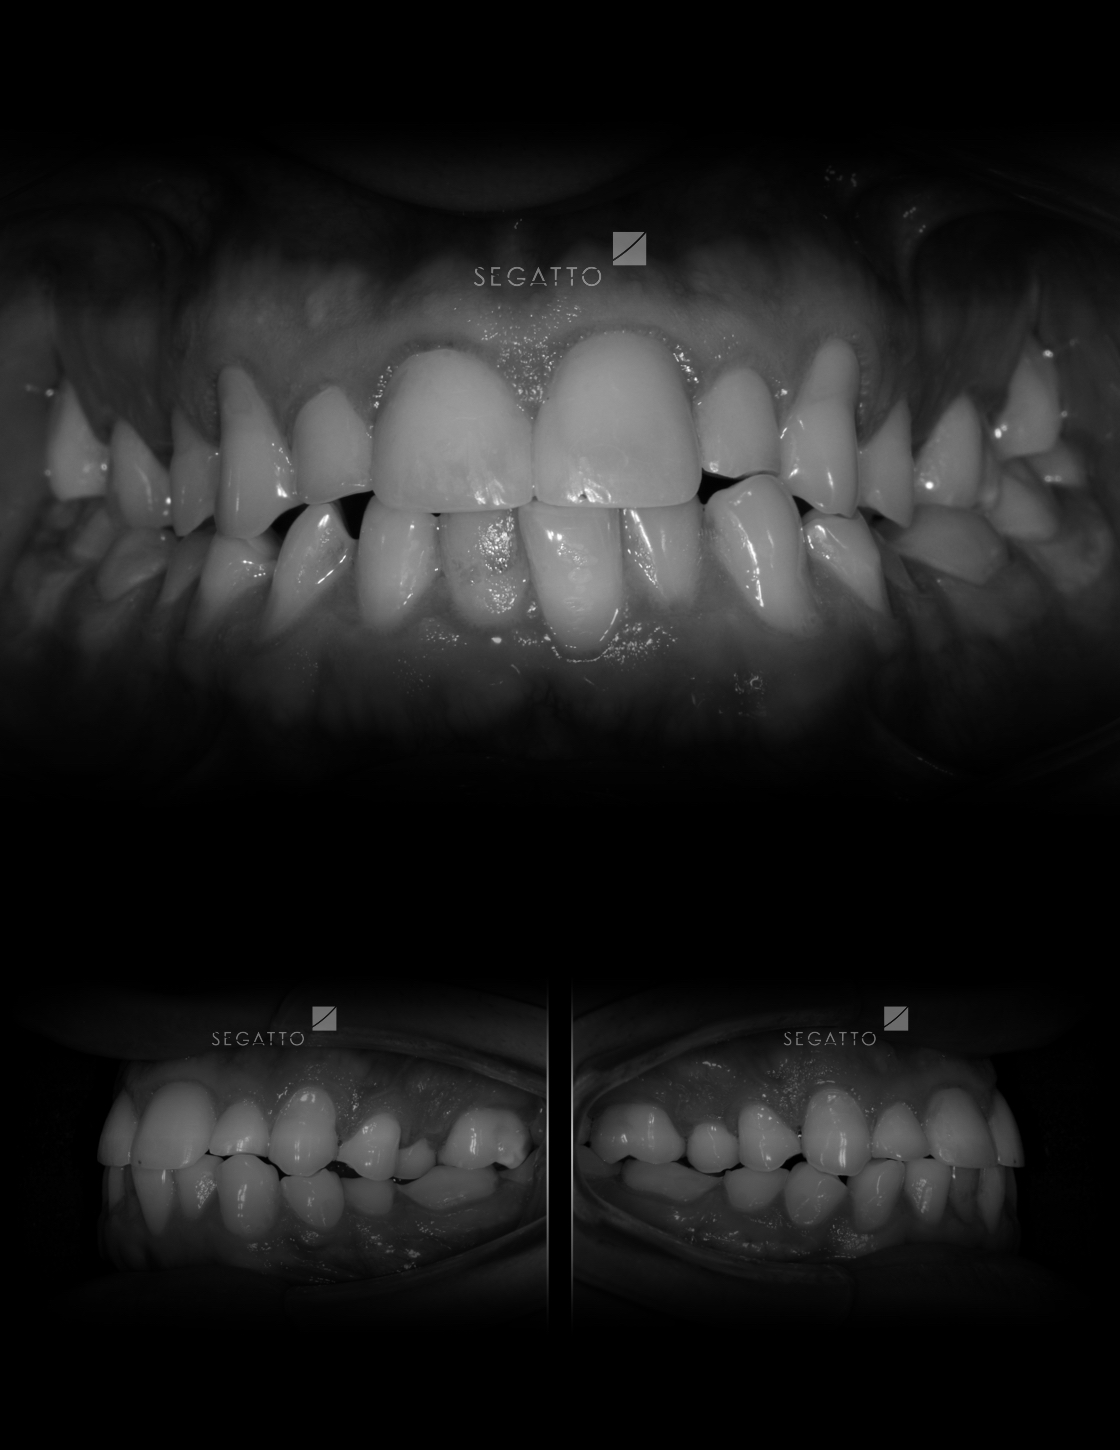

Orthodontics

Cases